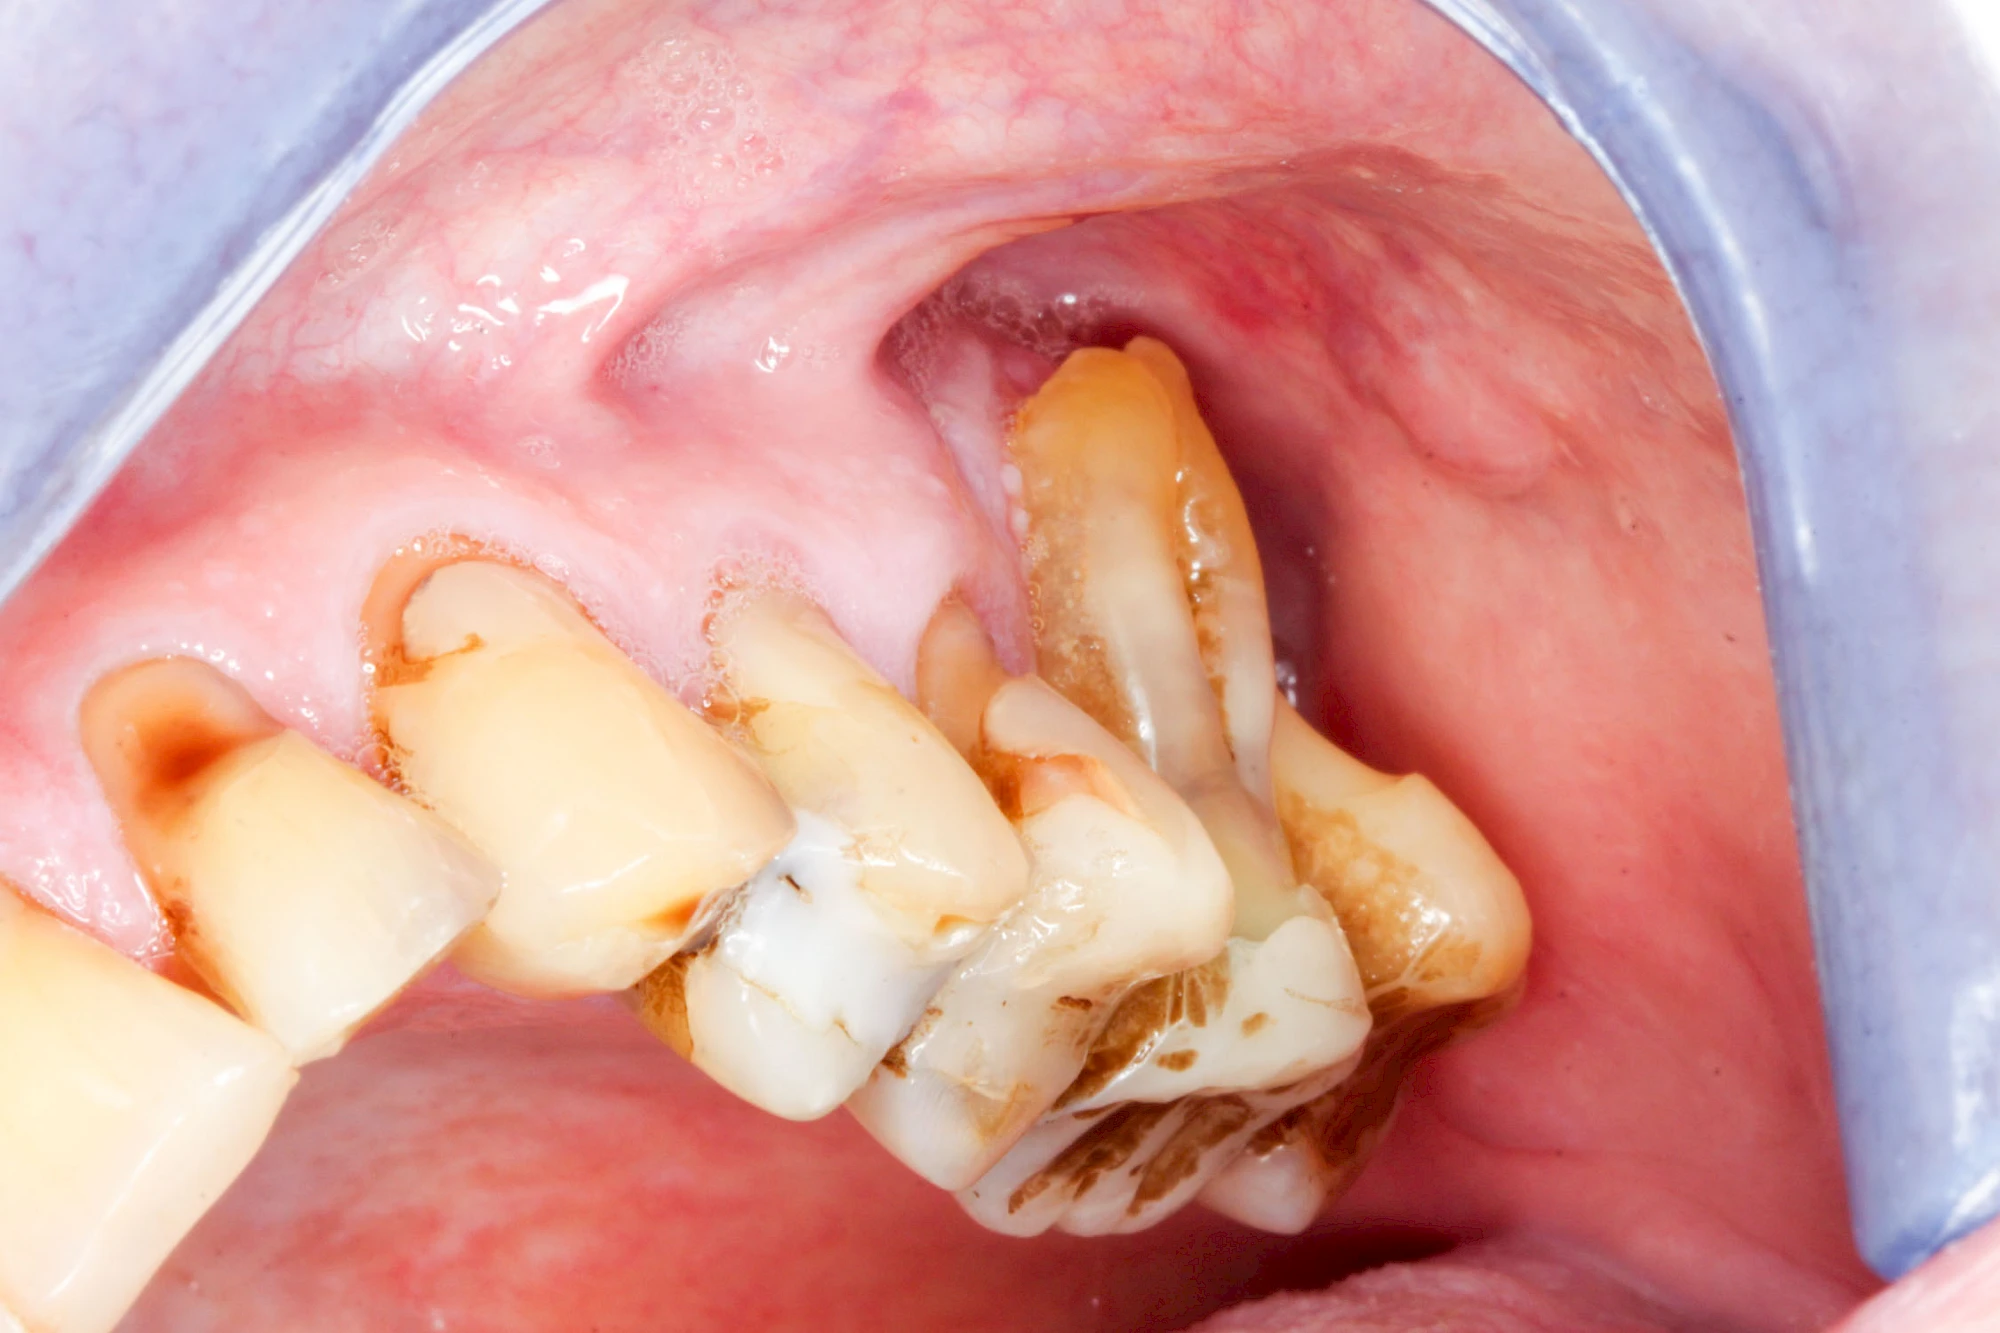

Ist zunächst nur das Zahnfleisch von der Entzündung betroffen, spricht man von Gingivitis. Später, wenn auch der Knochen um die Zähne herum entzündet ist, spricht man von einer Parodontitis. Bei der Parodontitis wird der Knochen nach und nach abgebaut und das Zahnfleisch zieht sich zurück. Die Zahnhälse und Zahnwurzeloberflächen liegen mehr und mehr frei. Die Zähne werden zunehmend lockerer und fallen schließlich aus.